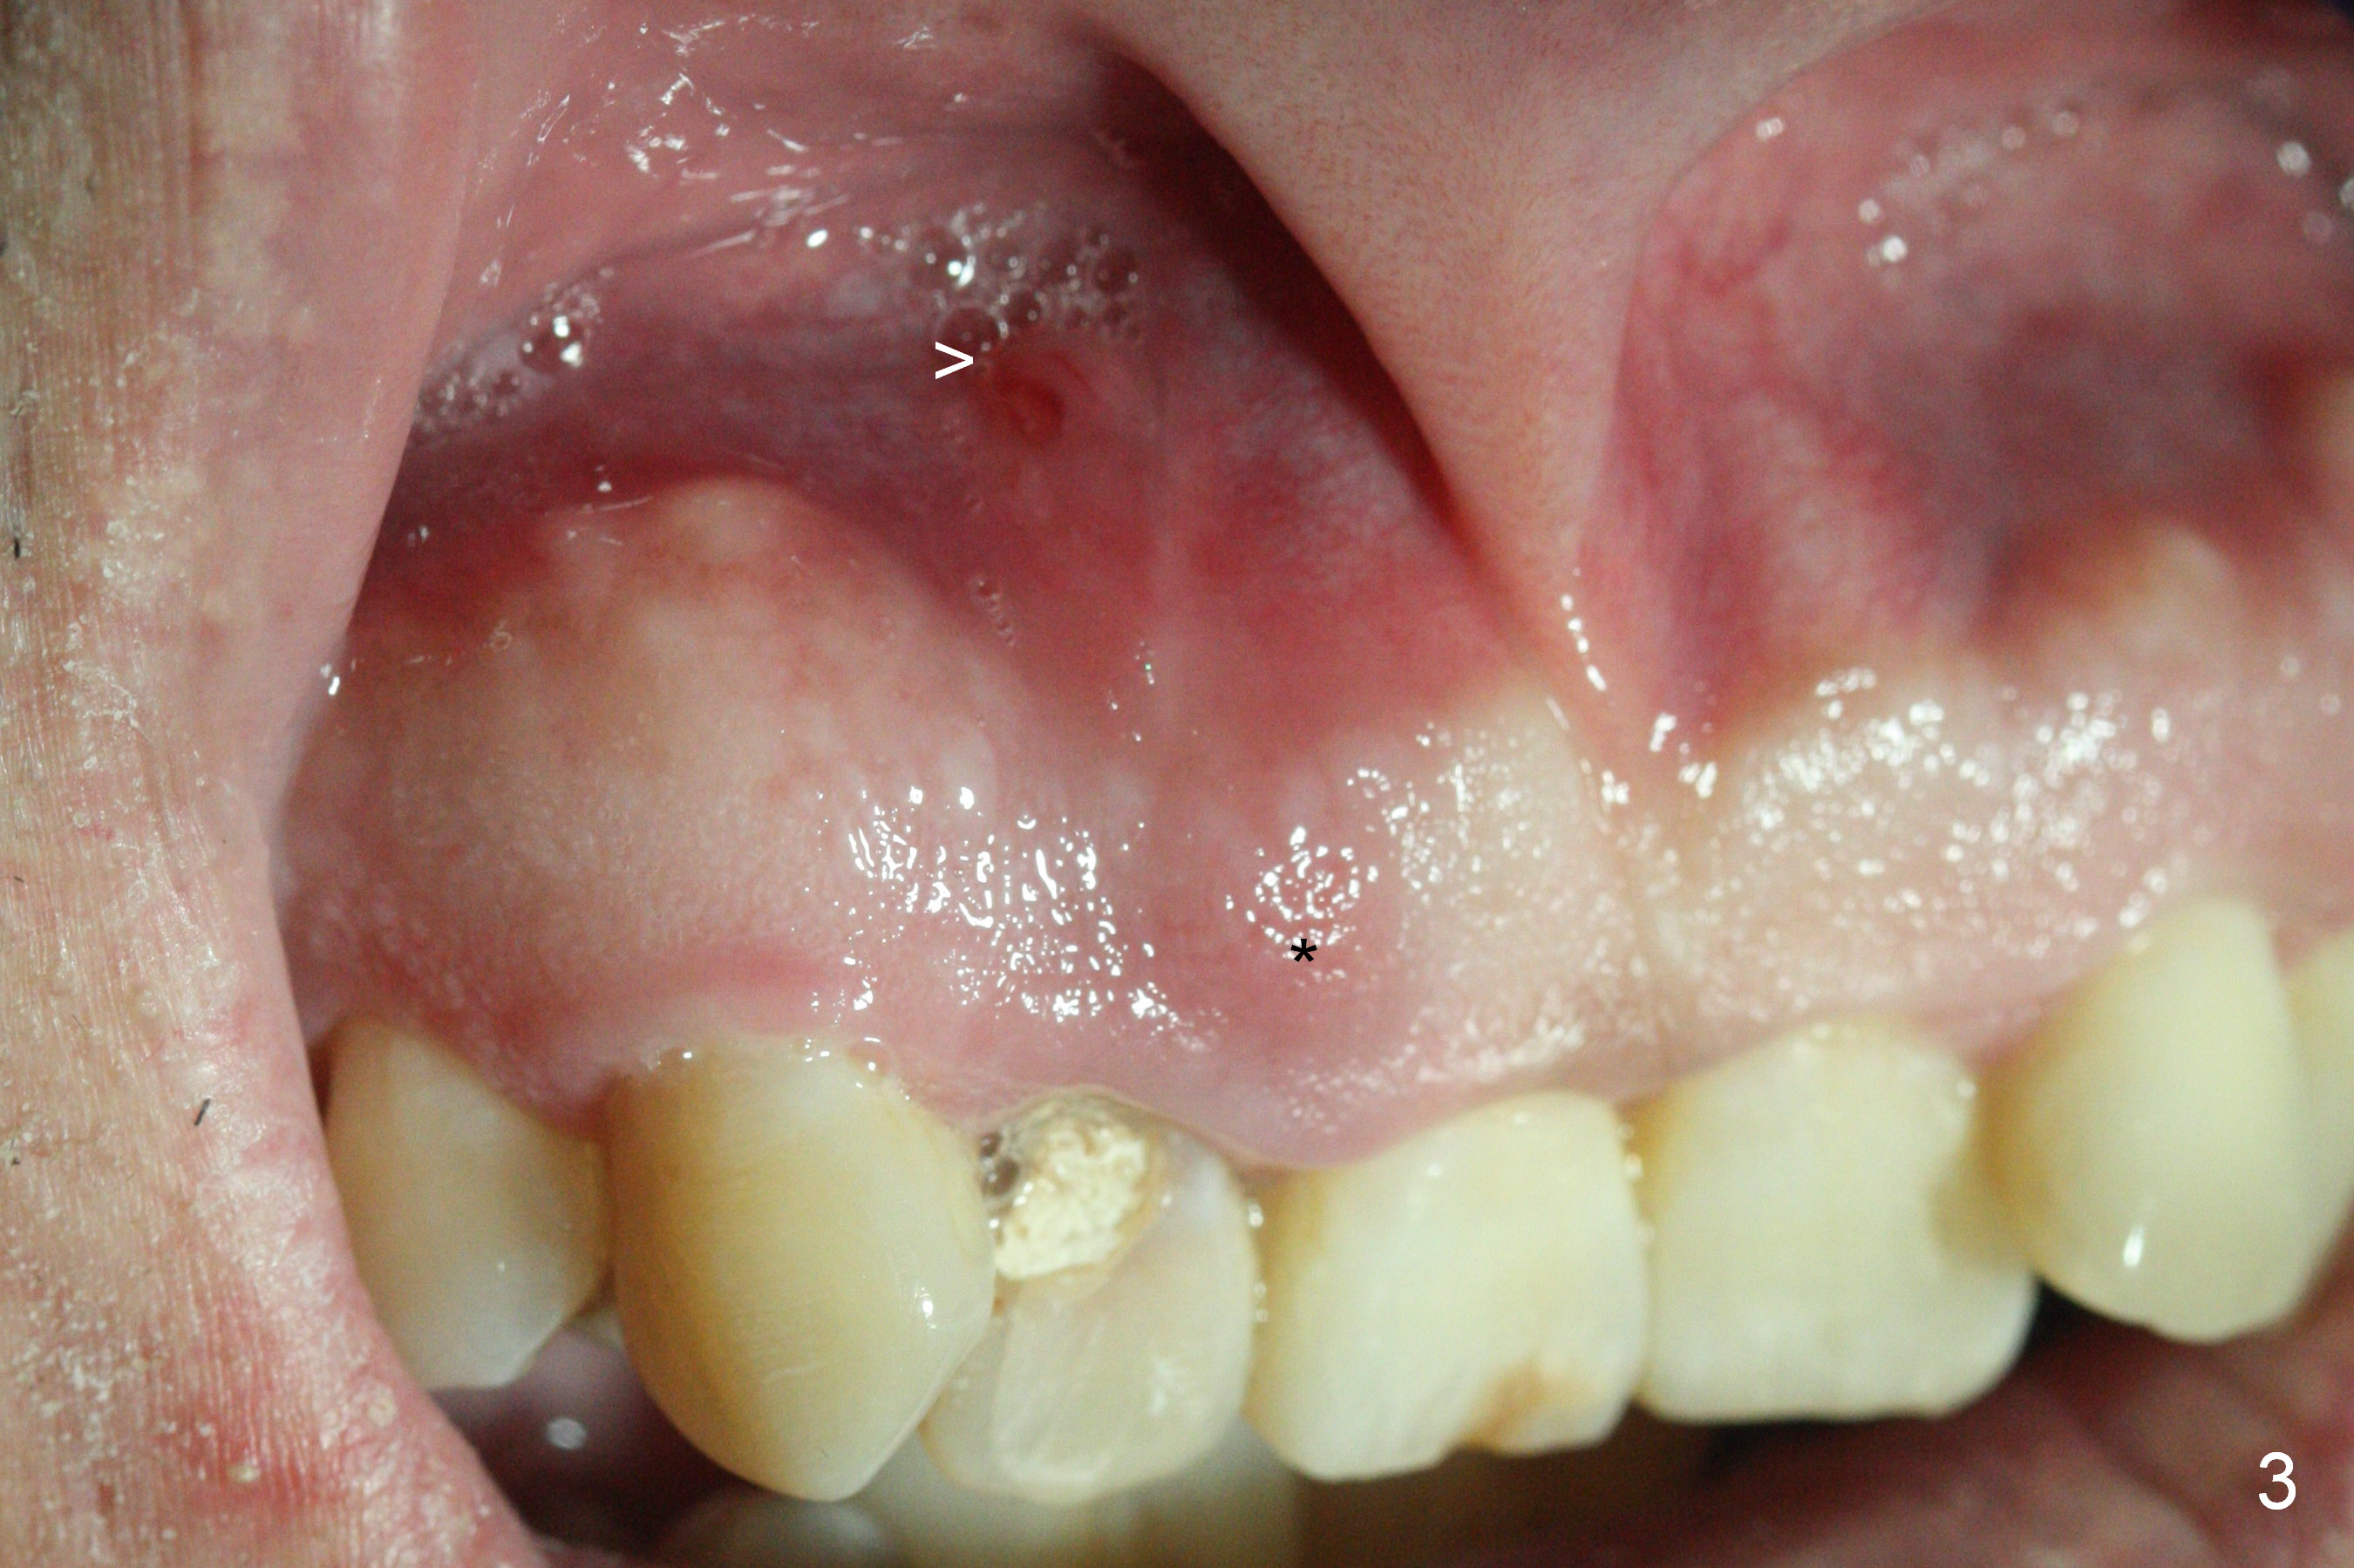

A 52-year-old man had a non-restorable lateral incisor 3 years ago (Fig.1). It fractures lately (Fig.2) with a buccal abscess (Fig.3 *) ) and fistula (>, possible severe buccal plate defect, prepare PRF). Severe deep bite (Fig.4) and malocclusion (Fig.5) will present a challenge to implant provisional restoration.

After extraction (no Antibiotic socket treatment), start osteotomy in the palatal wall for a few mm in the native bone, insert a parallel pin and check bite. Adjust the trajectory and position of the osteotomy as early as possible. If the bone is dense, extend osteotomy depth to 18 mm for a 3.8x15 or 16 implant. Otherwise 20 mm for 3.8x18 mm one. The final drill will be 2-3 mm shorter if the bone density is low.